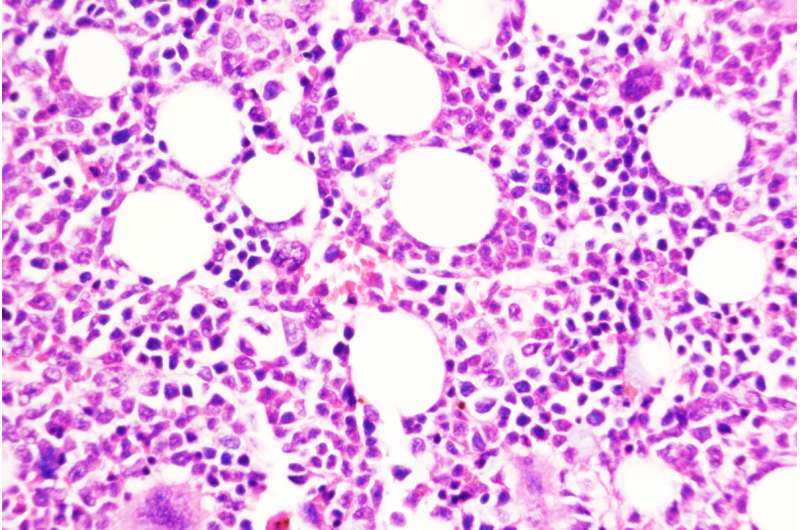

一种慢性白血病可以潜伏多年。一些患者可能需要治疗来控制这种类型的血液癌症——骨髓增生性肿瘤(MPN),而另一些患者可能需要经过长时间的观察等待。但对于一小部分患者来说,这种缓慢的疾病可能会转变为一种侵略性的癌症,称为继发性急性髓系白血病,这种癌症几乎没有有效的治疗方案。人们对这种转变是如何发生的知之甚少。

研究人员对这些肿瘤的遗传学进行了深入研究,包括在缓慢的慢性阶段和在患者服用JAK2抑制剂时疾病转化为侵袭性形式之后。在本研究分析的40例肿瘤患者中,DUSP6基因高度表达。

使用遗传技术删除DUSP6基因可以防止这种癌症模型小鼠向侵袭性疾病的转变。研究人员还测试了一种抑制DUSP6的药物化合物,并发现这种化合物(仅用于动物研究)在两种不同的癌症小鼠模型和从患者身上取样的人类肿瘤小鼠中阻止了慢性疾病向侵袭性疾病的进展。在这些模型中,通过基因和药物降低DUSP6水平也能减少炎症。